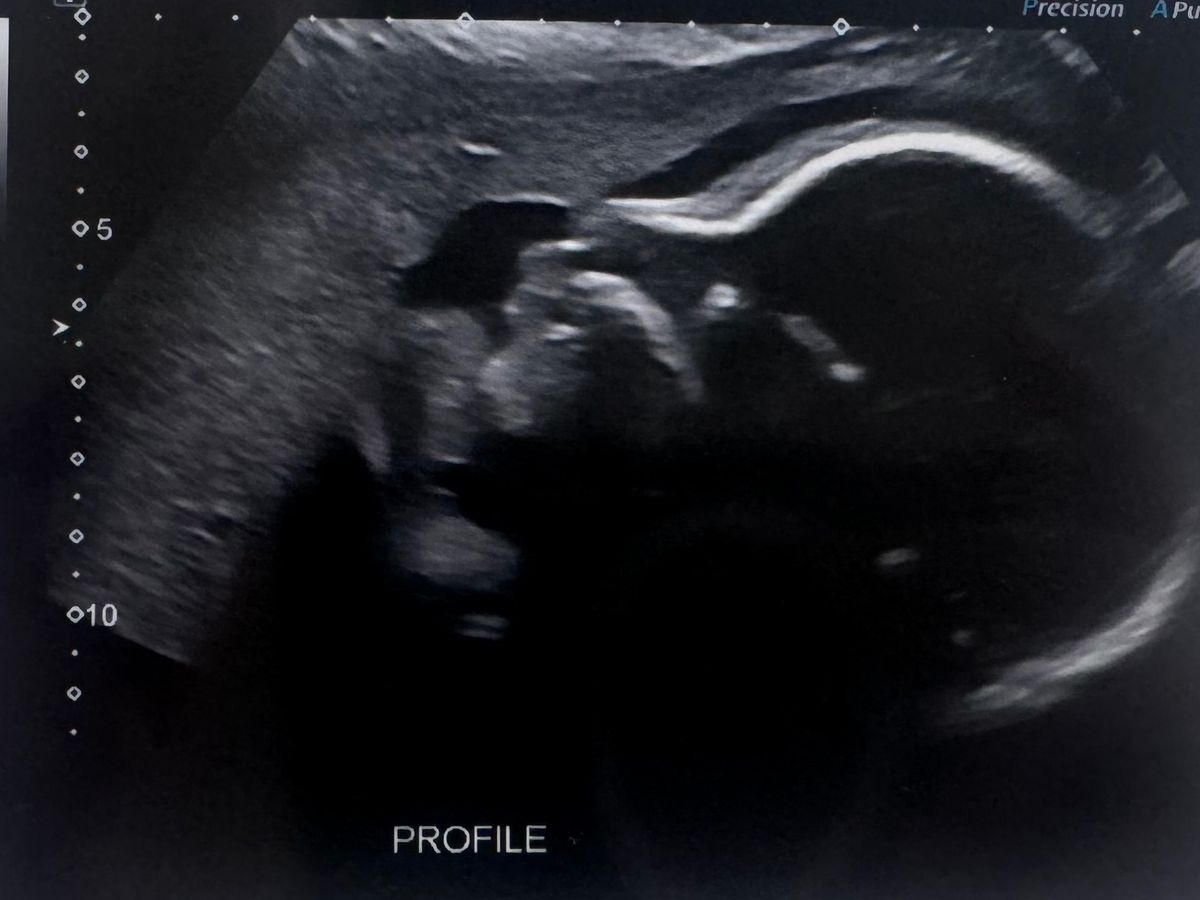

Hi, my name is Michelle and I am fundraising for my daughter Jordan and her husband Justin. Jordan and Justin have been together for 10 years and married for 2 years. They have been trying for a baby ever since, they were over the moon to find out they were pregnant in February 2024. On their 20 week scan the doctors discovered that Baby G has Transposition of the great arteries, VSD, pulmonary artesia and will require heart surgery within days of his/her birth.